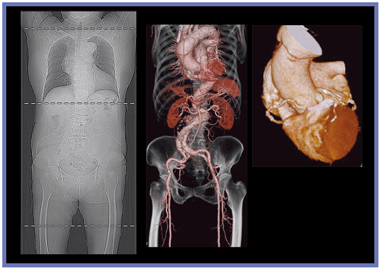

図1にvHPで撮影した当院での症例を示す。患者は胸痛を訴えて来院したため,胸部を心電同期で6秒(HP32),腹部を非同期で4秒(HP91),合計10秒で撮影した。胸部と腹部の境目に段差のない,良好な画像が得られている。また,心電同期撮影を行った胸部はブレやアーチファクトもなく,LADのプラークも明瞭に描出されている。ハーフ再構成のためノイズが多くなるが,AIDR 3Dを使用することで,それが抑えられている。

![]() 図1 vHPを用いた胸腹部の心電同期・非同期撮影 |